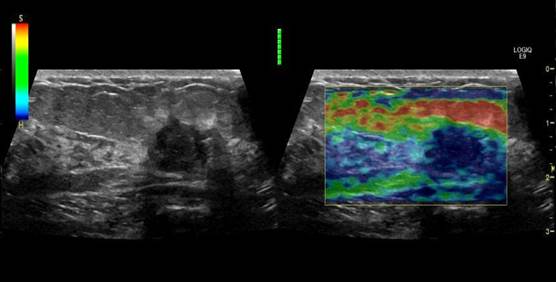

Elastography - компрессионная эластография. Режим позволяет произвести качественное сравнения жесткости тканей, что является очень полезным инструментом онкологии. Режим строится поверх В-режима, внутри зоны (окна) интереса и окрашивается в соответствии с шкалой жесткости. Доступен на узи сканерах начиная с высокого класса.

Shear Wave - эластография сдвиговых волн. Режим позволяет произвести количественный анализ жесткости тканей и является незаменимым в диагностике опухолевых образований и исследованиях печени. Режим строится поверх В-режима, внутри зоны (окна) интереса и окрашивается в соответствии с шкалой жесткости. Доступен на узи сканерах начиная с экспертного класса и полноценно функционирует только на премиум классе.